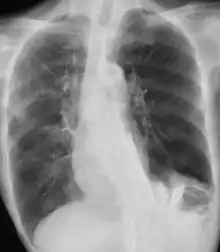

| Chest X-ray in a case of COPD exacerbation where a nasopharyngeal swab detected Haemophilus influenzae, with right-sided opacities | |

A chest X-ray is usually performed on people with fever and, especially, hemoptysis (blood in the sputum), to rule out pneumonia and get information on the severity of the exacerbation. Hemoptysis may also indicate other, potentially fatal, medical conditions.[6]